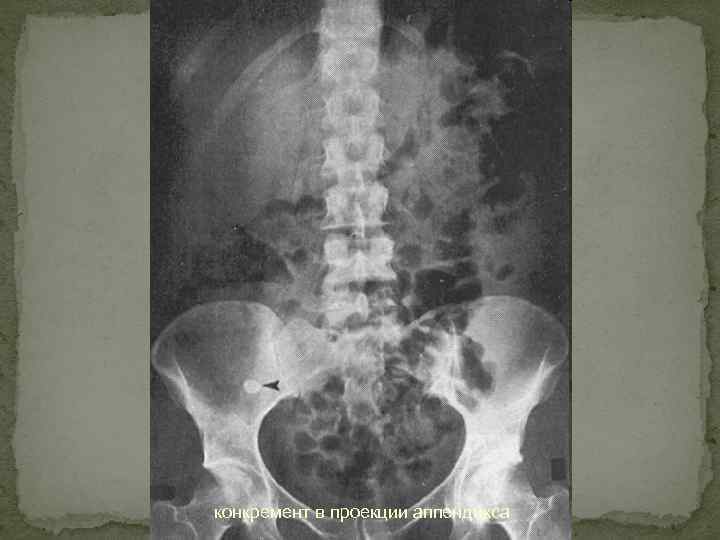

Инструменталдық әдістер Ø Шолу рентгенографияда оң жақ мықын аймағында үрленген ішекті немесе рентгенконтрасты нәжіс тастарын көруге болады. Ø Лапароскопияда қабынған құрттәрізді өсіндіне немесе қабынудың қосымша көріністерін табуға болады. Ø УДЗ жуандаған, ісінген құрттәрізді өсіндіні анықтайды. Ø Аппендэктомия Ø Компьютерлі томография

конкремент в проекции аппендикса